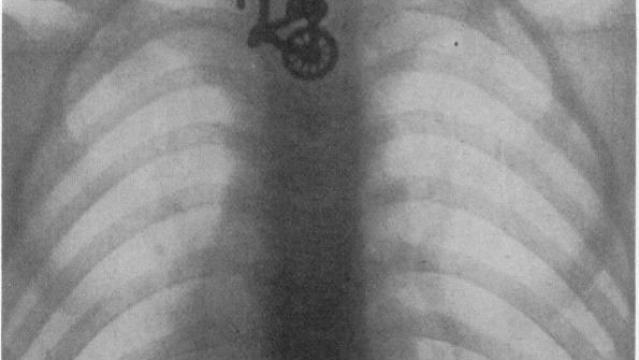

Radiografía del esófago de un niño que se tragó una bicicleta de juguete en 1906. | UCL

Entre lo más inaudito está una radiografía del esófago de un niño que se tragó una bicicleta de juguete en 1906 o el chaval de ocho años, diagnosticado con hiperactividad, que se tragó durante meses los perdigones de los gansos que cazaba y comía su familia como parte de un juego con su hermano.